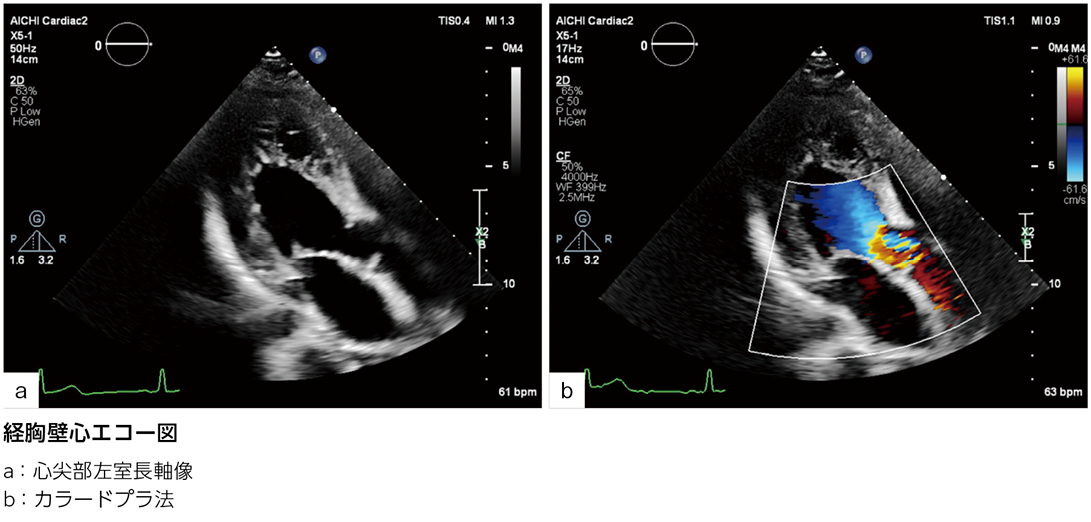

その後当院にて術後フォローアップとなり,経胸壁心エコー図検査で左室流出路最大血流速度4.0m/秒(ドプラ法による圧較差64mmHg)と上昇を認めた。無症状。